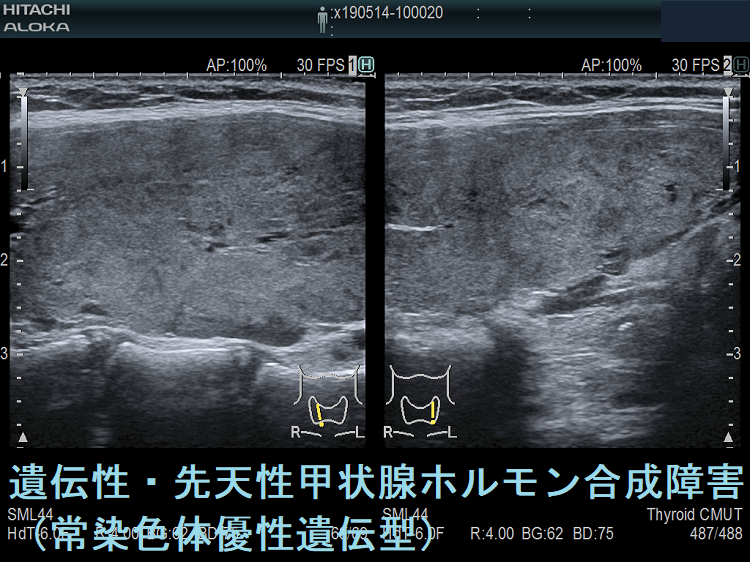

ケース①

ケース②

ケース③

ケース④

日本の遺伝性甲状腺ホルモン合成障害は外国に比べると軽症が多い。その理由として、日本人はヨウ素(ヨード)摂取量が多く、甲状腺ホルモンの原料に欠かないためと考えられています。

遺伝性甲状腺ホルモン合成障害で、サイログロブリン異常症(サイログロブリン遺伝子異常症)以外は、血中サイログロブリンが上昇するにも関わらず、甲状腺自体の破壊性変化に乏しく、マシュマロ様の軟らかい腺腫様甲状腺腫の形態を取る事があります。

遺伝性甲状腺ホルモン合成障害の超音波(エコー)画像は色々なパターンがあります。

- 常染色体優性遺伝型;腺腫様甲状腺腫の形態になります。

- 常染色体劣性遺伝型;新生児マススクリーニングで見つかり、適切に治療された場合、甲状腺サイズは正常、内部は低エコーで、甲状腺ホルモンをほとんど作っていないのが分かります。